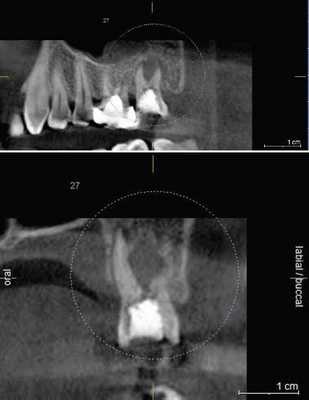

2. Патологии в периапикальных тканях

Наиболее частым патологическим состоянием, затрагивающим зубы является воспалительные процессы пульпы и периапикальных областей. Технология КЛКТ теперь предоставляет клиницисту возможность обозревать нужную зону в трех различных плоскостях, тем самым получая 3D информацию. Поражения, заключенные в губчатом веществе кости с малым количеством или отсутствием кортикальной пластинки, на обычной пленке могут быть диагностированы с большим трудом. Lofthag-Hansen, Stavropoulos и Wenzel сравнили точность получаемых данных при КЛКТ с ограниченным FOV и обычными снимками.

Ученые сообщили, что КЛКТ предоставляет более точные диагностические данные (61%) по сравнения с цифровыми (39%) и обычными (44%) рентгенограммами. Но, несмотря на то, что данные КЛКТ являются более точными, исследователи не призывают к полному вытеснению обычной внутриротовой рентгенографии для выявления периапикальных изменений в обычной клинической практике из-за финансовой и вредностной составляющих. Estrela и коллеги предложили использовать периапикальные индексы, основанные на КЛКТ, для идентификации патологий (Фото 4-6).

Фото 5: Хронические периапикальные абсцессы около первого правого нижнего моляра

Фото 6: Поражение периодонтальных тканей около левого верхнего второго моляра

Система индексов КЛКТ состоит из 6 ступеней (0-5), исходящих из определения самого большого размера повреждения в каком либо из измерений, и принятие в расчет расширение и разрушение кортикальной кости.

Применяя данный индекс, Low пришел к выводу, что в обнаружение периапикальных патологий лучше использовать КЛКТ недели обычную рентгенографию.

КЛКТ с градиентом теней может оказать помощь в дифференциальном диагнозе кисты и гранулемы. В целом способность выявлять патологии у КЛКТ так же высока, как и у простой КТ. Этот способ может стать важным для пациентов, обращающихся с болевым синдромом или с неточно локализованными жалобами в области ранее леченных или не леченных зубов, на обычном рентгене которых патология не выявляется.